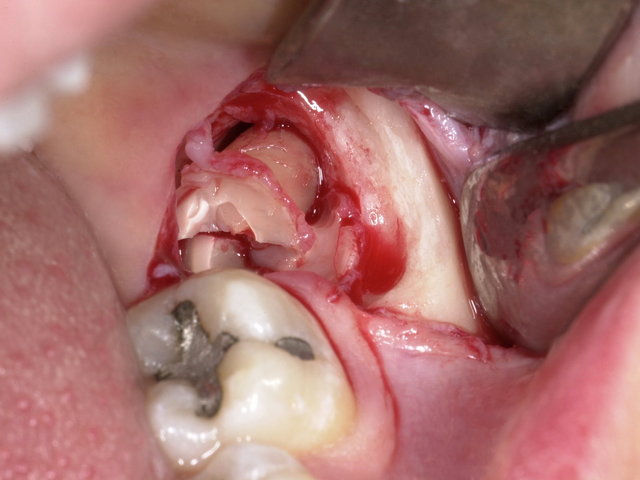

Operative Weisheitszahn-Entfernung ... ✓

Operative Weisheitszahn-Entfernung ...